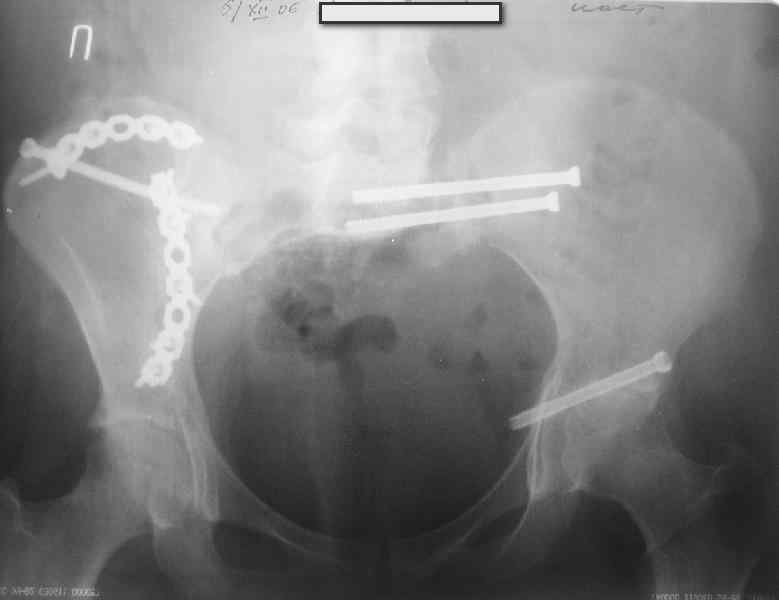

В приложении снимки при поступлении и послеоперационные год назад.

Могу сказать одно: миграция винтов и нестабильность синтеза левого подвздошно-крестцовогоо сочленения очевидна.

Вот цитата из статьи с odoс.ru:"Идеально было бы иметь винты диаметром 7 - 8 мм с довольно широкой резьбой в 50 - 80 мм. Также необходимы более длинные винты и, в общем, наиболее часто используемые размеры - между 90 и 150 мм." Думается, в этой статье вы найдете ответы на все ваши вопросы.

были использованы винты 7.2 мм, кроме того иетодика транссакральной фиксации не является общепринятой и широко рекомендуемой, но и в этих случаях они наблюдали случаи вторичного смещения

Забыл добавить, что ИХМО показан реостеосинтез более длинными винтами, с более широкой резьбой, с фиксацией за правое подвдошно-крестцовое сочленение.